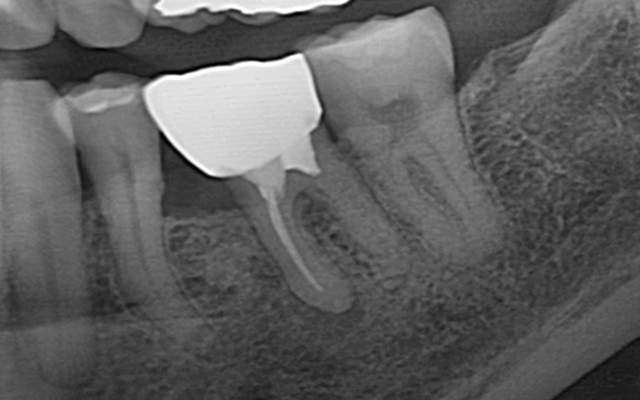

신경치료는 감염되거나 손상된 치수(신경·혈관)를 제거하고

뿌리관 내부를 소독·밀폐하여 치아를 기능적으로 보존하는 치료입니다.

감염 재발을 막기 위해 정밀 진단·무균 술식·밀폐가 핵심입니다.

| 진단·계획 | 치근단 엑스레이 기반 | CT 및 확대 시야 기반의 정밀 진단 |

| 예후 관리 | 정기 내원 권장 | 정기 엑스레이 추적·교합/보철까지 일괄 관리 |